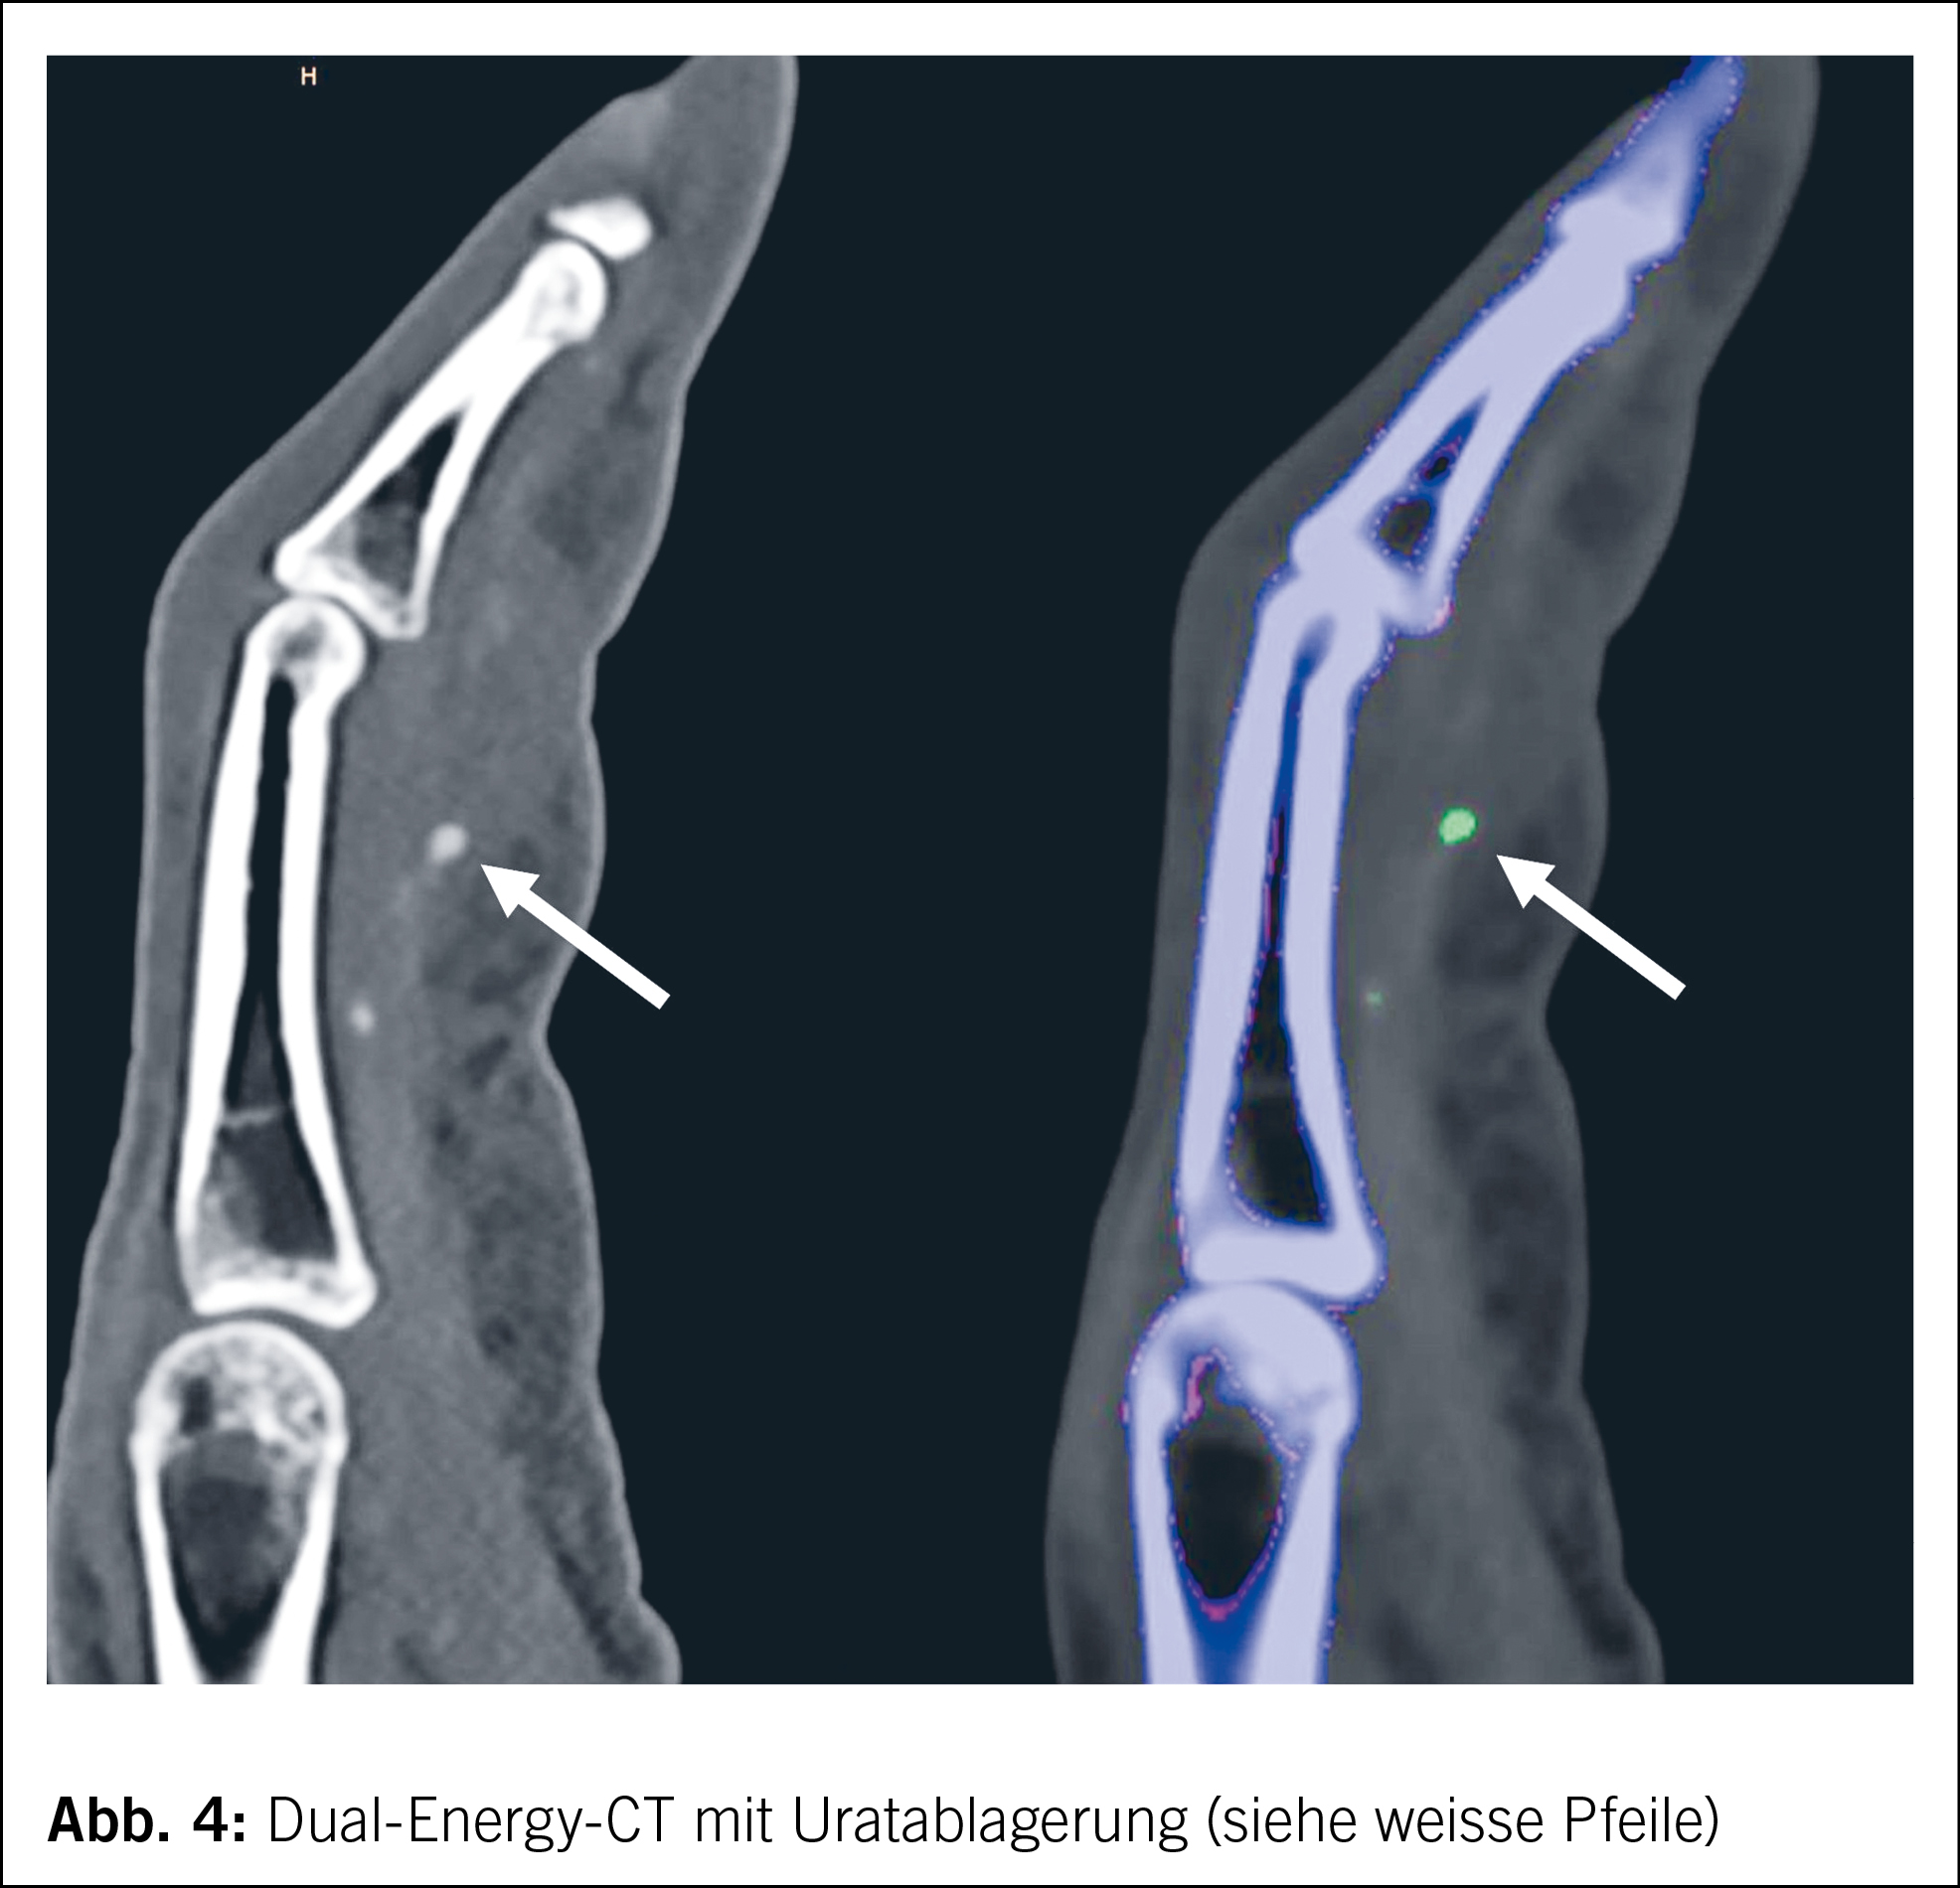

In der ergänzend durchgeführten Dual-Energy Computed Tomography (DECT) der Hände zeigte sich eine kleine Uratablagerung in der Sehnenscheide um die Flexorsehne des Mittelfingers auf Höhe der Phalanx proximalis des dritten – biopsierten – Fingers (Abb. 4).